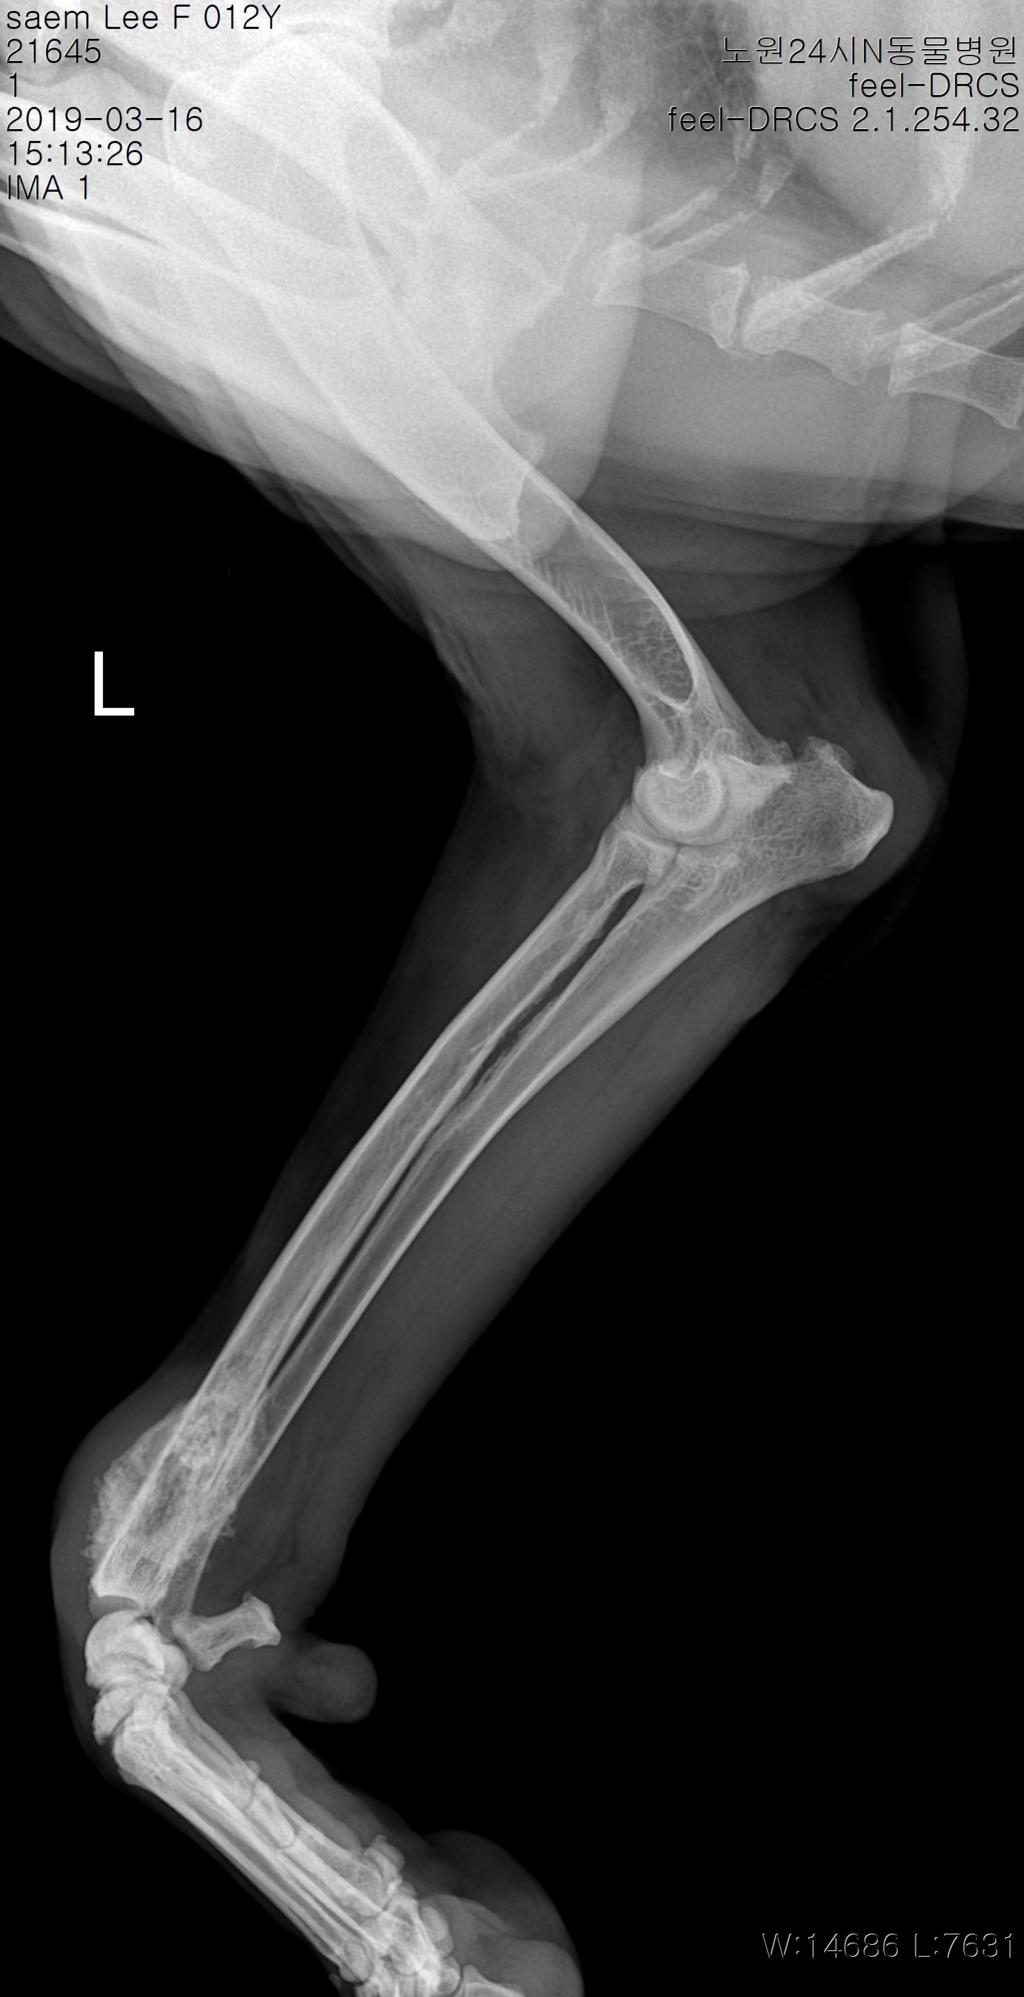

What does pelvic pain from ovarian cancer feel like? Do you believe your eating habits to be healthy? Does bone cancer pain start suddenly? Pain is the most common sign of bone cancer, and may become more noticeable bone pain can cause a dull or deep ache in a bone or bone region (e.g., back, pelvis, legs, ribs, arms). Bone cancer most commonly affects the long bones in the arms and legs.

Bone Scan What Does It Show from i0.wp.com Common symptoms of cancer treatment for. Do you believe your eating habits to be healthy? Do we know why the bone behaves this way? Additional symptoms of bone cancer can include unexplained weight loss and fatigue, mayo clinic adds. Pain caused by bone cancer usually begins with a feeling of tenderness in the affected bone. This gradually progresses to a persistent ache or an ache in some cases, the cancer can weaken a bone, causing it to break (fracture) easily after a minor injury or fall. What does a cancer lump feel like? In the beginning, it is hard to recognize bone cancer, but the first common problem that can be recognized is a severe pain felt at night during normal movements.